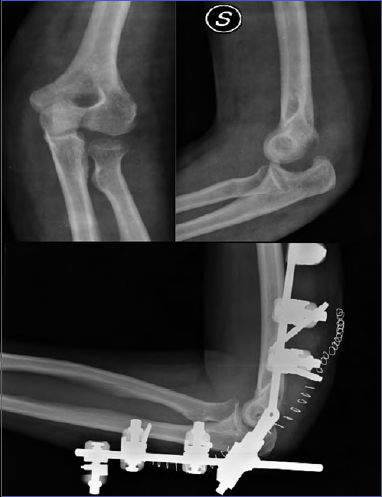

Persistent soft tissue

Persistent soft tissue dislocations are relatively rare and include missed diagnosis (or neglected forms) that is rare in developed countries and the forms caused by an inappropriate or failed treatment. In the failed treatment forms, where a re-dislocation occurs in a plaster cast or in a brace, diagnosis can be delayed if a strict clinical and/or radiographic follow-up is not performed. When the joint has been dislocated for longer than 2-3 weeks, it can no longer be reduced conservatively. Treatment requires extended arthrolysis and repair or reconstruction of the collateral ligaments combined or not with the use of an external fixator (Fig. 1). The reconstruction of the ligaments with autologous or homologous grafts is usually required after 3 months or more of dislocation.

Figure 1.A case of persistent soft tissue instability, treated with extended arthrolysis, collateral ligaments repair and the use of an external fixator, to protect the ligament repair in the immediate follow-up.